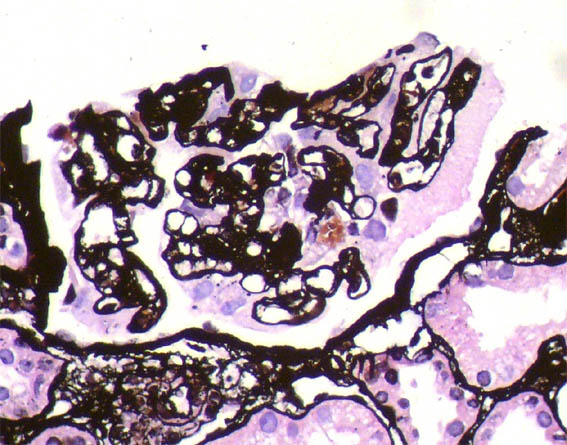

Figure 8. Methenamine-silver, X400.

Figure 9. Methenamine-silver, X400.

Figure 10. Methenamine-silver, X400.